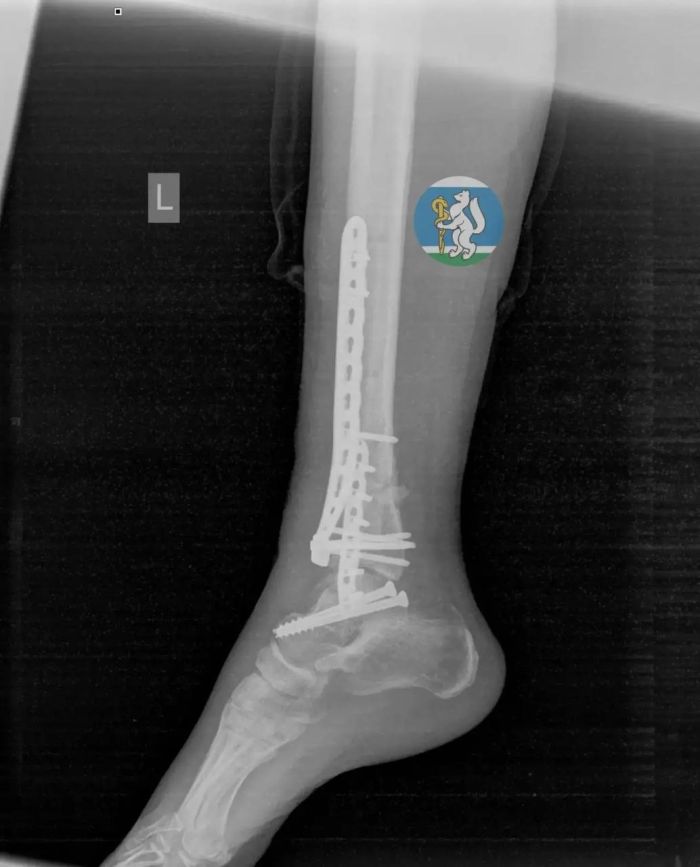

У пострадавшей диагностировали черепно-мозговую травму, повреждение позвоночника, переломы таза и ноги, а также травмы грудной клетки и лёгких. Врачи экстренно вывели её из шока, остановили кровотечение и провели сложную операцию.

После этого женщина находилась в реанимации на ИВЛ, затем перенесла ещё одно вмешательство. Благодаря поэтапному лечению и ранней реабилитации она снова начала двигаться. Спустя месяц пациентку выписали, сейчас она проходит восстановление.